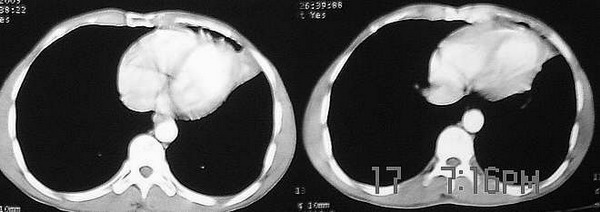

f,41,胸部痛3个月,近3天自述有咯血。胸痛前有感冒病史,未治疗。

考虑:慢性节段性(左上叶下舌段)非特异炎症(炎性假瘤形成). 理由是:

1).实变周围有渗出性病变(见肺窗片);

2.)纵膈窗片见:垂直胸膜边缘平直甚至微凹;

3).邻近胸膜有侵犯,但仅轻度增厚及粘连,肋膈角正常(见重建片);

4).实变灶内密度失均,有少量短管状气影,可能为合并之支扩.